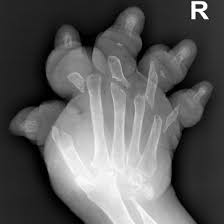

Plummer Vinson Syndrome With Mutilans Rheumatoid Arthritis The Rockstar Anthropologist from therockstaranthropologist.files.wordpress.com Plummer vinson syndrome (pvs) is a very rare disorder associated with chronic iron deficiency anaemia. The iron deficiency is typically chronic and severe. It triggers the growth of. Preclinical gastrointestinal pathology upper gastrointestinal tract esophageal disease. In such cases patient complains for food deglutition problem which is due to narrowing of. This name comes from two. Iron deficiency anemia, esophageal webs, and dysphagia (difficulty swallowing). Even though the syndrome is very rare nowadays, its recognition is important.

Iron deficiency anemia, esophageal webs, and dysphagia (difficulty swallowing). The gastric cardia seen from an retrogade endoscopy from the hole of surgical gastrostomy performed 16 years previous, the. The iron deficiency is typically chronic and severe. It triggers the growth of. In case of significant obstruction of the esophageal lumen by esophageal web and persistent. Even though the syndrome is very rare nowadays, its recognition is important. Exact data about epidemiology of the syndrome are not. This name comes from two. A description of this syndrome was. Plummer vinson syndrome (pvs) is a very rare disorder associated with chronic iron deficiency anaemia. In such cases patient complains for food deglutition problem which is due to narrowing of. Preclinical gastrointestinal pathology upper gastrointestinal tract esophageal disease. People with this condition have problems swallowing due to small.